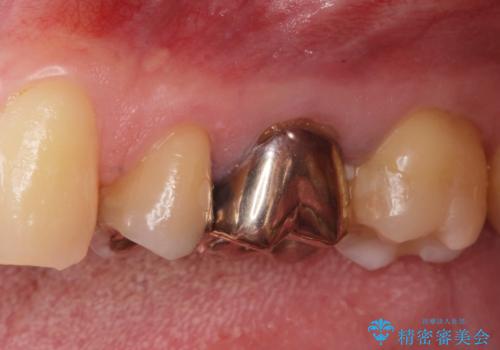

- ジルコニアクラウンスタンダード・仮歯 13.2万円費用は治療当時の料金となります

白い被せ物が入り大変満足して頂きました。

現在他の部位も検討中です。